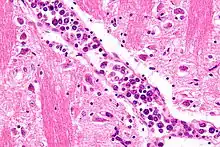

| Micrograph showing an intravascular large B-cell lymphoma in a blood vessel of the brain. H&E stain. | |

The diagnosis of IVBCL is heavily dependent upon obtaining biopsy specimens from involved tissues, particularly the skin but in cases without skin lesions, other apparently involved tissues. Microscopic examination of these tissues typically shows medium-sized to large-sized lymphocytes located within small- to medium-sized blood vessels of the skin, lung, and other tissues or the sinusoids of the liver, bone marrow, and spleen. On occasion, these malignant cells have the appearance of Reed-Sternberg cells. The lesions should show no or very little extension outside of blood vessels. As determined by immunohistochemistry analyses, the intravascular malignant lymphocytes express typical B-cell proteins, particularly CD20, which is found in almost all cases, CD79a and Pax5, which are found in most cases,[5] and MUM1 and Bcl-2, which are found in 95% and 91% of cases, respectively.[2] These B-cells are usually (80% of cases) non-germinal center B-cells (see Pathophysiology section) and may express one or more of the gene, chromosome, and gene expression abnormalities described in the above Pathophysiology section. Since the classical variant can present with a wide range of clinical signs, symptoms, and organ involvements, its presence may not be apparent, particularly in cases that do not exhibit clinically apparent skin lesions. Accordingly, random skin biopsies have been used to obtain evidence of IVL in cases that have signs and/or symptoms of the disease that are restricted to non-cutaneous sites,[2] even in cases that present with no other finding except unexplained fever.[17] The diagnosis of IVBCL, classical variant is solidified by finding these pathological features in more than one site.[2]